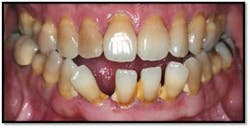

Tissue is light pink, tight and firm. All pockets are 1-3mm, no BOP

Charting shows that all pockets are now generalized 1-3 mm with no BOP

The patient is thrilled with her outcome and now has a stable dentition.

She is ready to move forward with orthodontia and will continue with periodontal supportive therapy every 3 months.